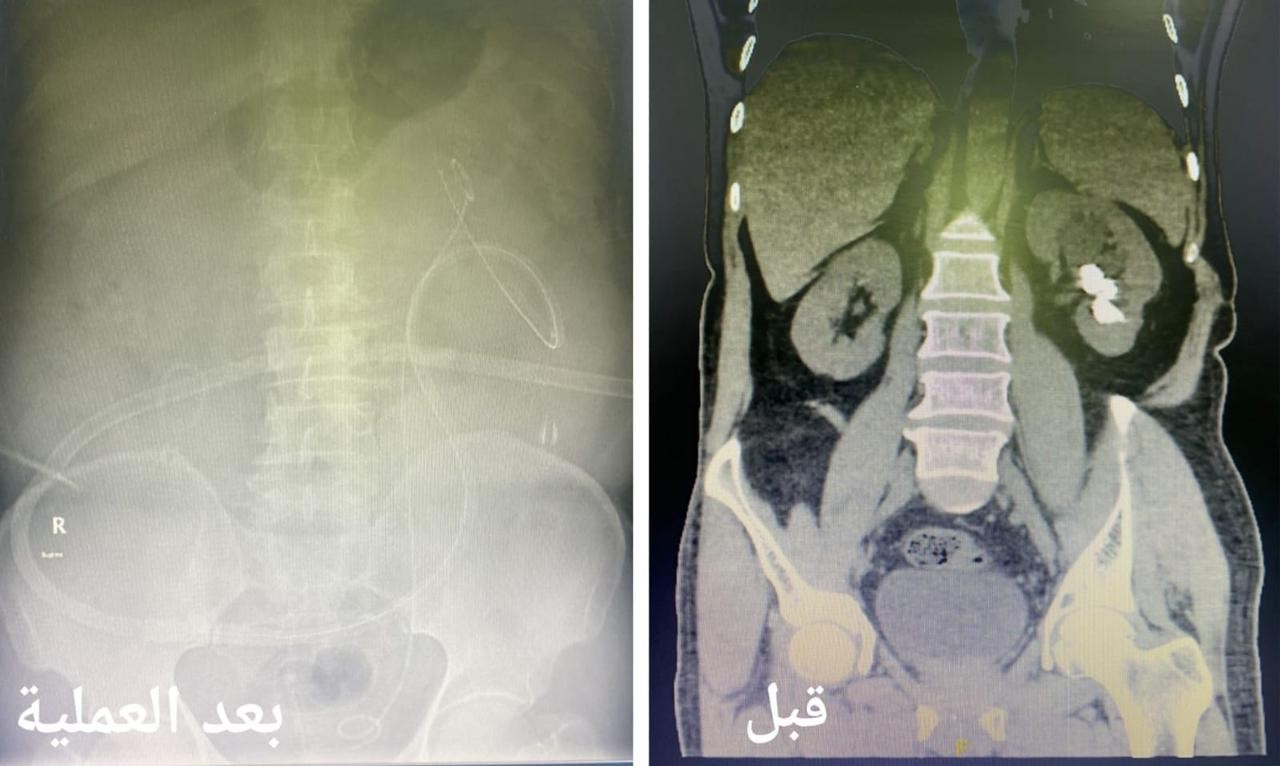

وأكدت أن الآم إزدادت خلال الأشهر الأخيرة مع المريض مع وجود تاريخ مرضي قديم يؤكد وجود حصوات في الجهاز البولي تسببت له تلك الاعراض مما استدعى سرعة إستكمال الفحوصات الطبية اللازمة والفحوص المخبرية للدم والبول والفحوص الإشعاعية التصويرية بالأشعة المقطعية تبين خلالها وجود حصوات في حوض وتجويف الكلية اليسرى بحجم 3 سنتيمتر.

وأضحت أنه تم تجهيز المريض ونقله لغرفة العمليات وعمل تدخل جراحي كلوي دقيق بشق سنتيمتر واحد في الجلد بإستخدام التقنيات الطبية الحديثة لإستئصال الحصوات في جلسة جراحية واحدة وإزالتها بالكامل بواسطة (المنظار الجلدي الكلوي) وجهاز التيليسكوب وأدوات طبية صغيرة الحجم حيث تم إغلاق الشق الجراحي بخياطة واحدة دون حدوث أي مضاعفات.